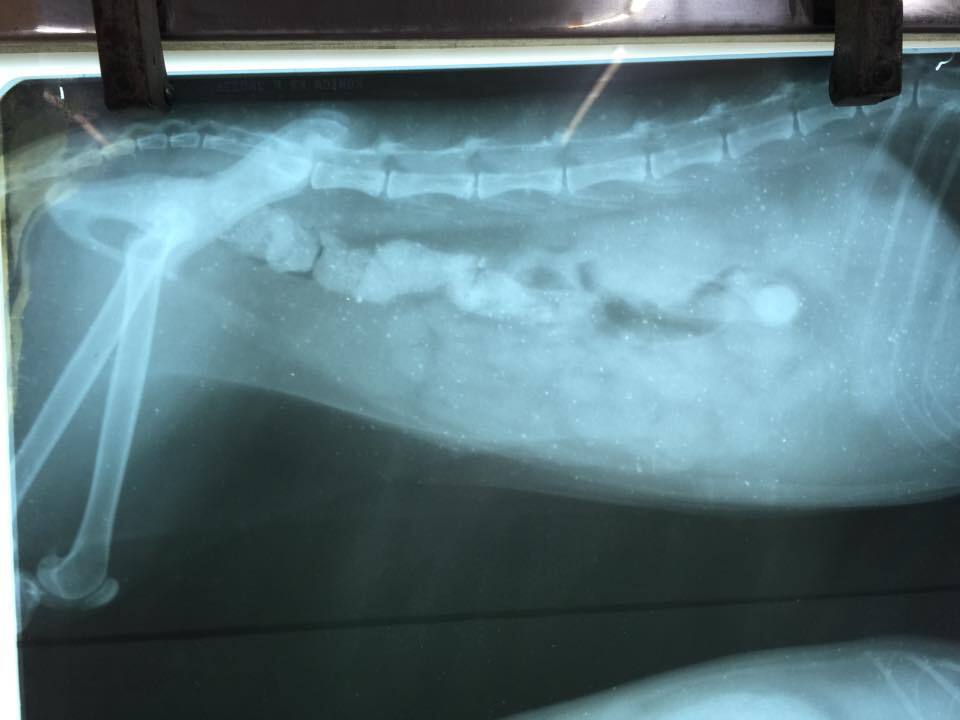

主題: 脫水虛弱走路不穩虎斑貓 申請者姓名: 許桂菱 花色: 申請日期: 2015-03-17 23:56:34 申請者部落格: 申請者臉書網址: 所在縣市/合作醫院: 彰化縣/成愛動物醫院 治療費用: 5230元 需求人數: 6人 已結案 (2015-04-14 17:29:36) 報名人員: fotojo(已付款)、Shu-Chun Yu(已付款)、黃小語(已付款)、陳昱先(已付款)、Tiffany Cheung x2(已付款)、 候補人員: 動物病情說明: 此母貓在餵養區不見蹤影10來天,本以為可能發生意外往生,3/5下班如常至餵養區,她卻出現但脫水消瘦及走路不穩歪斜,一度以為是否為後腳受傷,趕緊先向住戶要了紙箱,送醫檢查後醫生認為非腳傷,進行生化及二合一血檢,有貧血其他指數無特別異常,快篩有愛滋,貓無發燒但脫水虛弱無法自行進食,先施予點滴改善脫水及住院觀察!

3/10~3/12 照X光片確認骨頭沒有受傷,身體也無外傷,貓咪恢復自行進食,但是行走仍無力歪斜,醫生認為是神經問題,先補充B群營養

3/13出院帶至台中羅大宇醫院看診是否能做針灸治療,醫生認為可能是愛滋病毒造成的神經受損,目前以補充B群及改善貧血為優先!